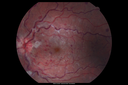

25 year old man with 1 week vision loss 20/16 OD 20/100 OS - CRVO

Heterozyrous for Factor V Leiden - Required 3 years of Lucentis - VA improved to 20/30. Able to stop therapy